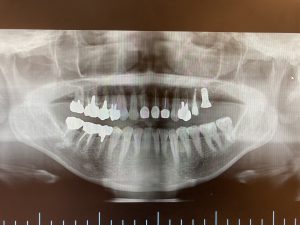

パノラマレントゲン写真を撮影したところ、左上7番目の歯の根が膿んでいることが疑われました。

パノラマレントゲンでははっきりした診断がつきませんでしたので、CTにてより正確な診断を行うこととしました。するとパノラマレントゲン写真では読影困難でしたが、CT画像では左上5番と7番の根の先に大きな病巣を認めました。

左上7番は歯の根が割れてしまっていましたので、残念ながら抜歯としました。左上6番にインプラント治療を計画しましたが、左上5番の病巣と近接しているため、まずは左上5番の根の治療をしっかり行い、治癒を確認した後にインプラント治療を行うこととしました。

根管治療は歯科用顕微鏡を用いて、徹底的に根の中の汚れを洗浄しました。根の中をキレイにした後、根の中に最終的な薬をつめて3ヶ月程治癒を待ちました。治癒後のCT画像がこちらです。左上5番の根の先にあった膿がキレイに治癒しているのが分かります。